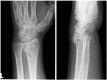

Background: The aim of this study was to compare the functional outcomes and complications of volar and dorsal plating for the management of intra-articular distal radius fractures, with special regard to indications for dorsal plating. Furthermore, we examine the rationale for choosing dorsal plating and its frequency of use.

Methods: Clinical assessments included range of motion measurements at the wrist; grip strength; the Quick Disabilities of the Arm, Shoulder, and Hand score; and the Gartland and Werley score. Clinical results were compared with those achieved using a volarly placed locking plate system. According to Lutsky's plate theory, the rationale for choosing dorsal plating was based on 4 types of pathologic fractures.

Results: Of 112 patients, 38 patients were treated with open reduction internal fixation via a dorsal approach and 68 patients were treated using a volar approach. Except for wrist flexion, there were no other statistical differences in the clinical results between groups for both subjective and objective parameters. There were no statistically significant differences in the complication rates between the volar and dorsal plated groups. One serious complication occurred after volar plating. The most common reason for choosing dorsal plating was irreducible dorsal die-punch fractures.

Conclusions: The treatment of displaced intra-articular distal radius fractures with a dorsally versus a volarly placed interlocking plate system demonstrated similar clinical results. Postoperative complications were not readily observed in the patients treated with a dorsal locking plate. Certain fracture patterns are more appropriately stabilized using a dorsal plate fixation.